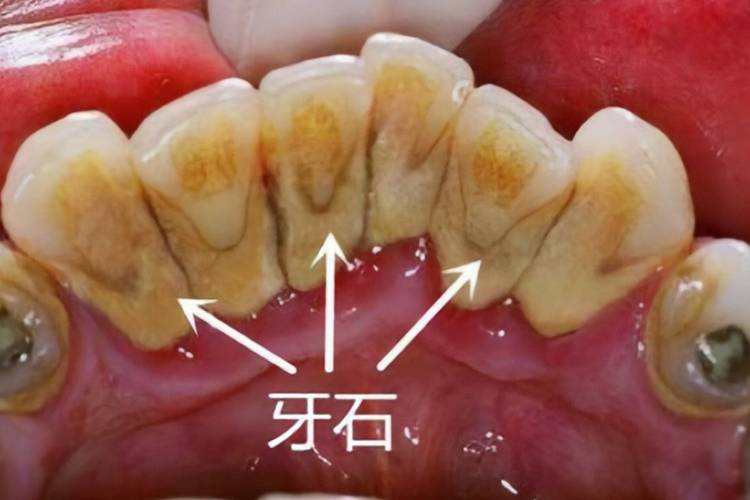

牙结石的形成是一个渐进的过程,始于牙菌斑的形成,牙菌斑是口腔中细菌与食物残渣、唾液成分混合形成的黏稠薄膜,附着在牙齿表面,尤其在牙龈边缘、牙面不易清洁的部位(如后牙的咬合面、牙齿邻面)更容易堆积,如果牙菌斑未能通过及时刷牙、使用牙线等方式被清除,它会与唾液中的矿物质(如钙、磷离子)结合,逐渐矿化变硬,形成牙结石,这一过程通常需要几天到几周的时间,初期呈软垢状,质地较软,颜色为乳白色或淡黄色,随着矿化程度增加,质地逐渐变硬,颜色加深,最终形成坚硬的牙结石,牙结石根据沉积位置可分为龈上结石和龈下结石:龈上结石位于牙龈缘上方,肉眼可见,通常呈黄色或棕色;龈下结石则位于牙龈缘下方,牙周袋内,颜色较深,呈褐色或黑色,且质地更坚硬,对牙周组织的危害更大。

牙结石对口腔健康的危害是多方面的,首先是引发牙龈炎,牙结石长期堆积在牙龈边缘,会不断刺激牙龈组织,导致牙龈充血、红肿、易出血,刷牙或咬硬物时出血是牙龈炎的典型表现,若不及时治疗,牙龈炎会进一步发展为牙周炎,牙结石中的细菌及其毒素会破坏牙周韧带和牙槽骨,导致牙周袋形成、牙龈萎缩、牙槽骨吸收,最终使牙齿松动、移位,甚至脱落,牙结石还可能影响美观,尤其是龈上结石明显时,会导致牙齿表面发黄、发黑,影响个人形象;长期存在的牙结石还可能引发口臭,因为细菌分解食物残渣会产生硫化物等异味气体。